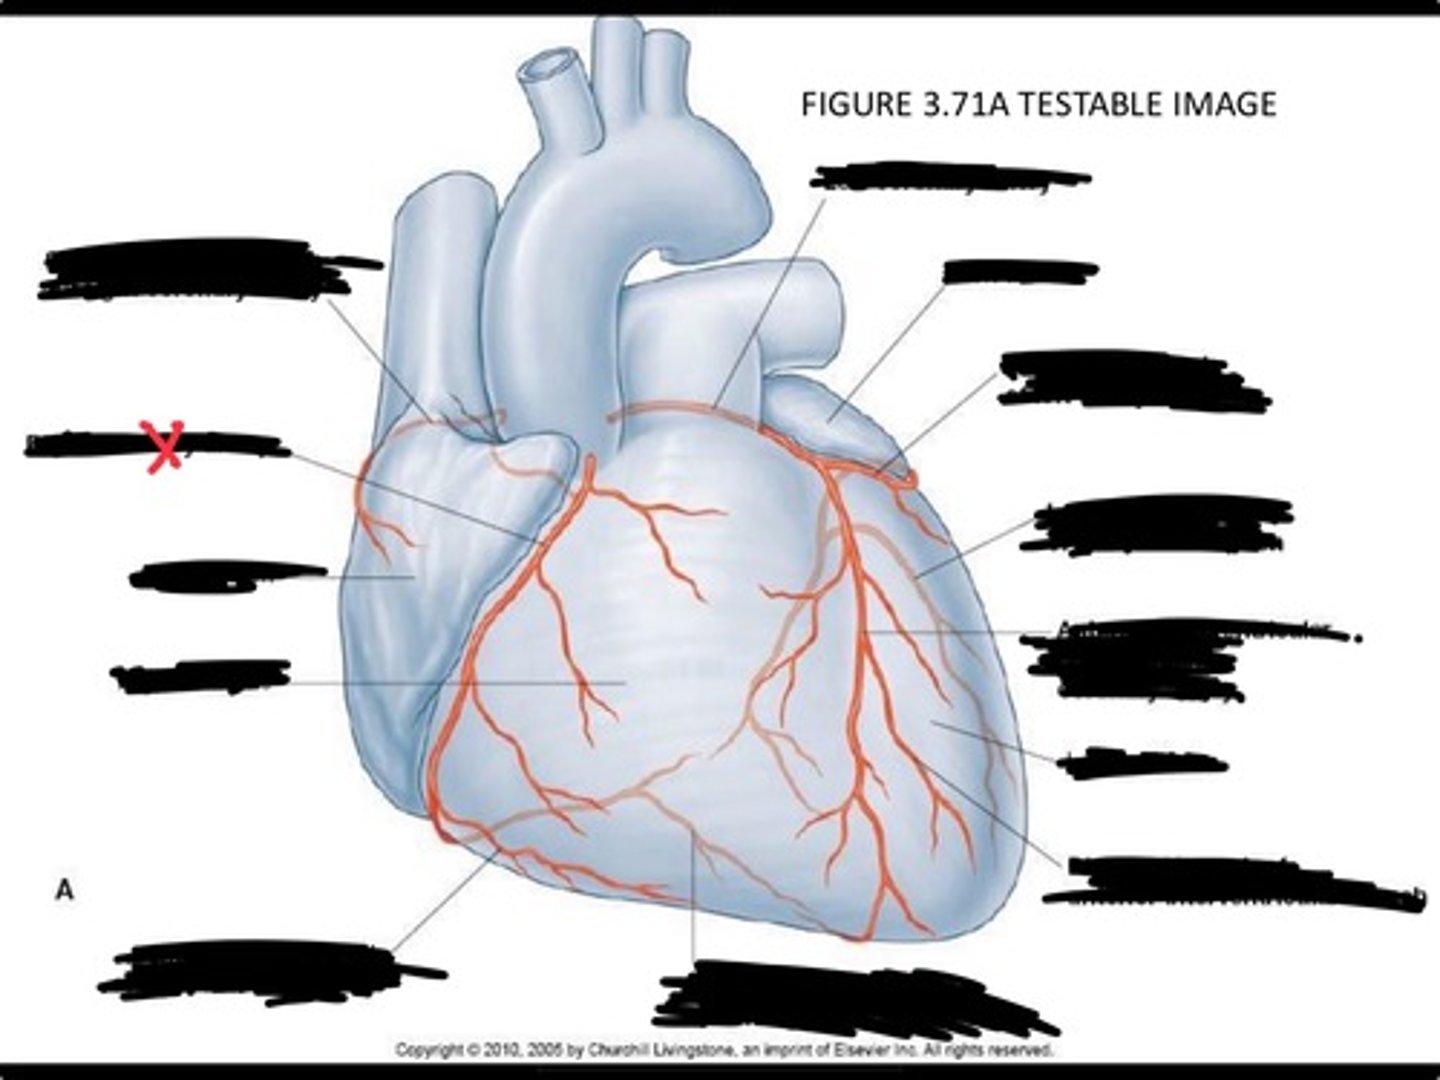

Posterior interventricular branch of right coronary artery

Right arginal branch of coronary artery

Right ventricle

Right atrium

Right coronary artery

Sinu-atrial nodal branch of right coronary artery

Left coronary artery

Left auricle

Circumflex branch of coronary artery